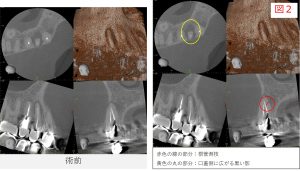

●レントゲン・CT画像所見

レントゲンおよびCT画像では、左上5番の根尖部に透過像(骨のない部分)が確認されました。

このような所見は、歯の内部で感染が生じ、根の先に炎症が存在している状態で、医学的には「根尖性歯周炎(こんせんせいししゅうえん)」と呼ばれます。

また、画像所見からは、歯の内部にスクリュータイプ(ネジ型)のメタルポスト(土台)が入っていることがわかりました。